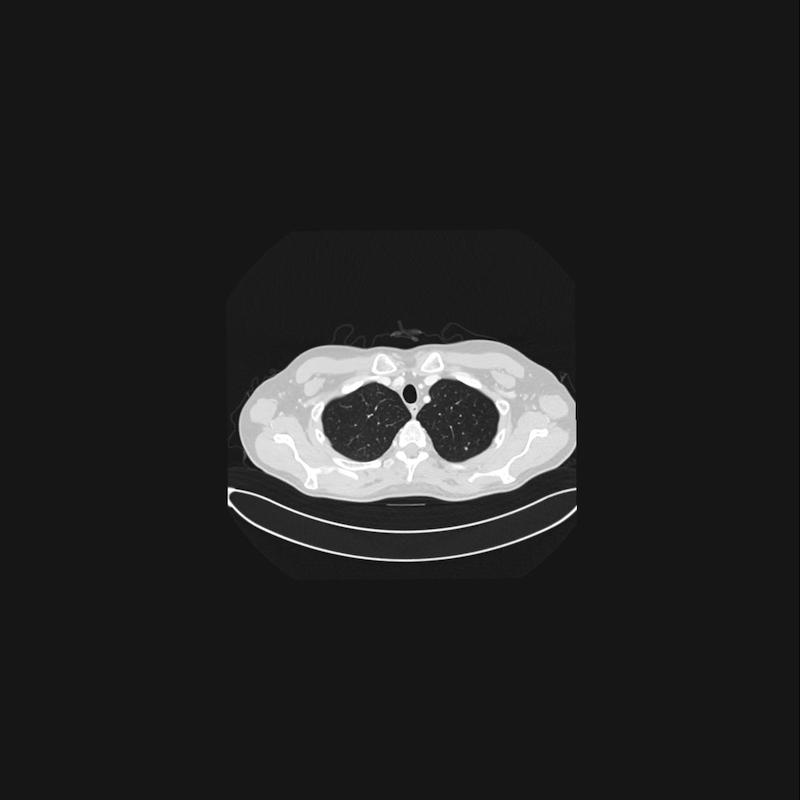

Dan foto’s die voor hen blijkbaar belangrijk zijn.

(dit is mijn long, waar ze ook een puntje zin zien, maar die groeit niet en is waarschijnlijk gewoon weefsel. Toch fijn dat ze het in de gaten houden)

En dat is ook zo, want op deze foto is te zien waar hij ligt (lieten ze ons zien)

In het midden zit een mooie stip (ader) En daar schuin boven zie je nog wat lichts (ook ader). Daar tussen zit een grijze klodder… dat is ‘m. De witte delen zijn aders, en daar moet hij dus los van komen te liggen.